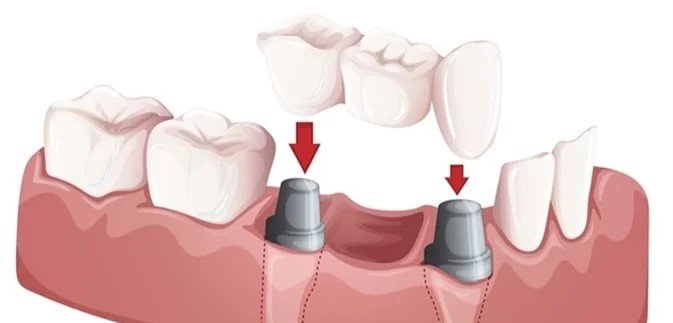

Replace missing teeth and restore your smile with our custom dental bridges. Our bridges are designed to look natural, function properly, and prevent the remaining teeth from shifting, providing a permanent solution for tooth loss.

- ✔ Implant-supported bridges